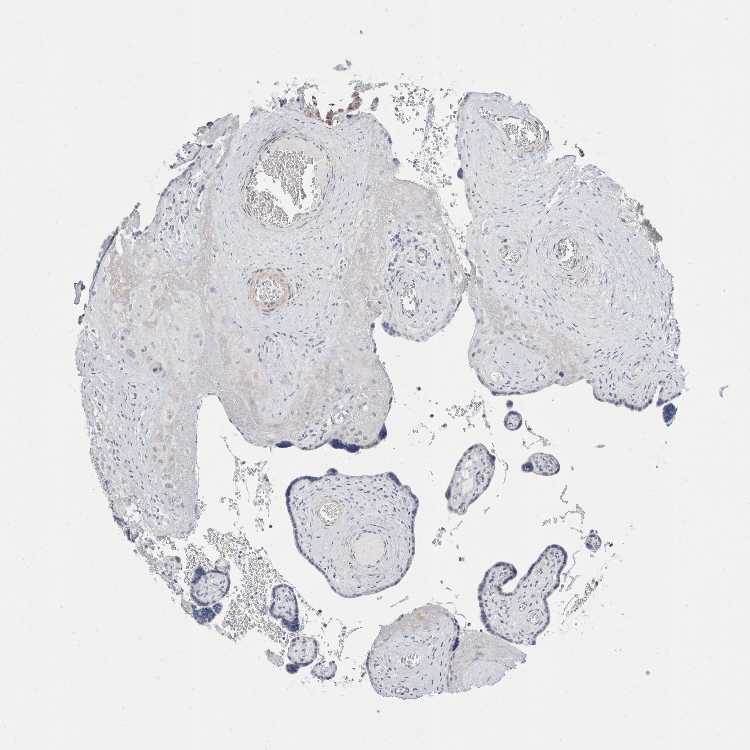

PLACENTA - Antibody stainingi

Antibody staining in the annotated cell types in the current human tissue is reported as not detected, low, medium, or high, based on conventional immunohistochemistry profiling in selected tissues. This score is based on the combination of the staining intensity and fraction of stained cells.

Each image is clickable and will lead to virtual microscopy that enables deeper exploration of all samples and also displays staining intensity scores, fraction scores and subcellular localization as well as patient and tissue information for each sample.

Antibody HPA024056

Decidual cells Not detected

Trophoblastic cells Not detected